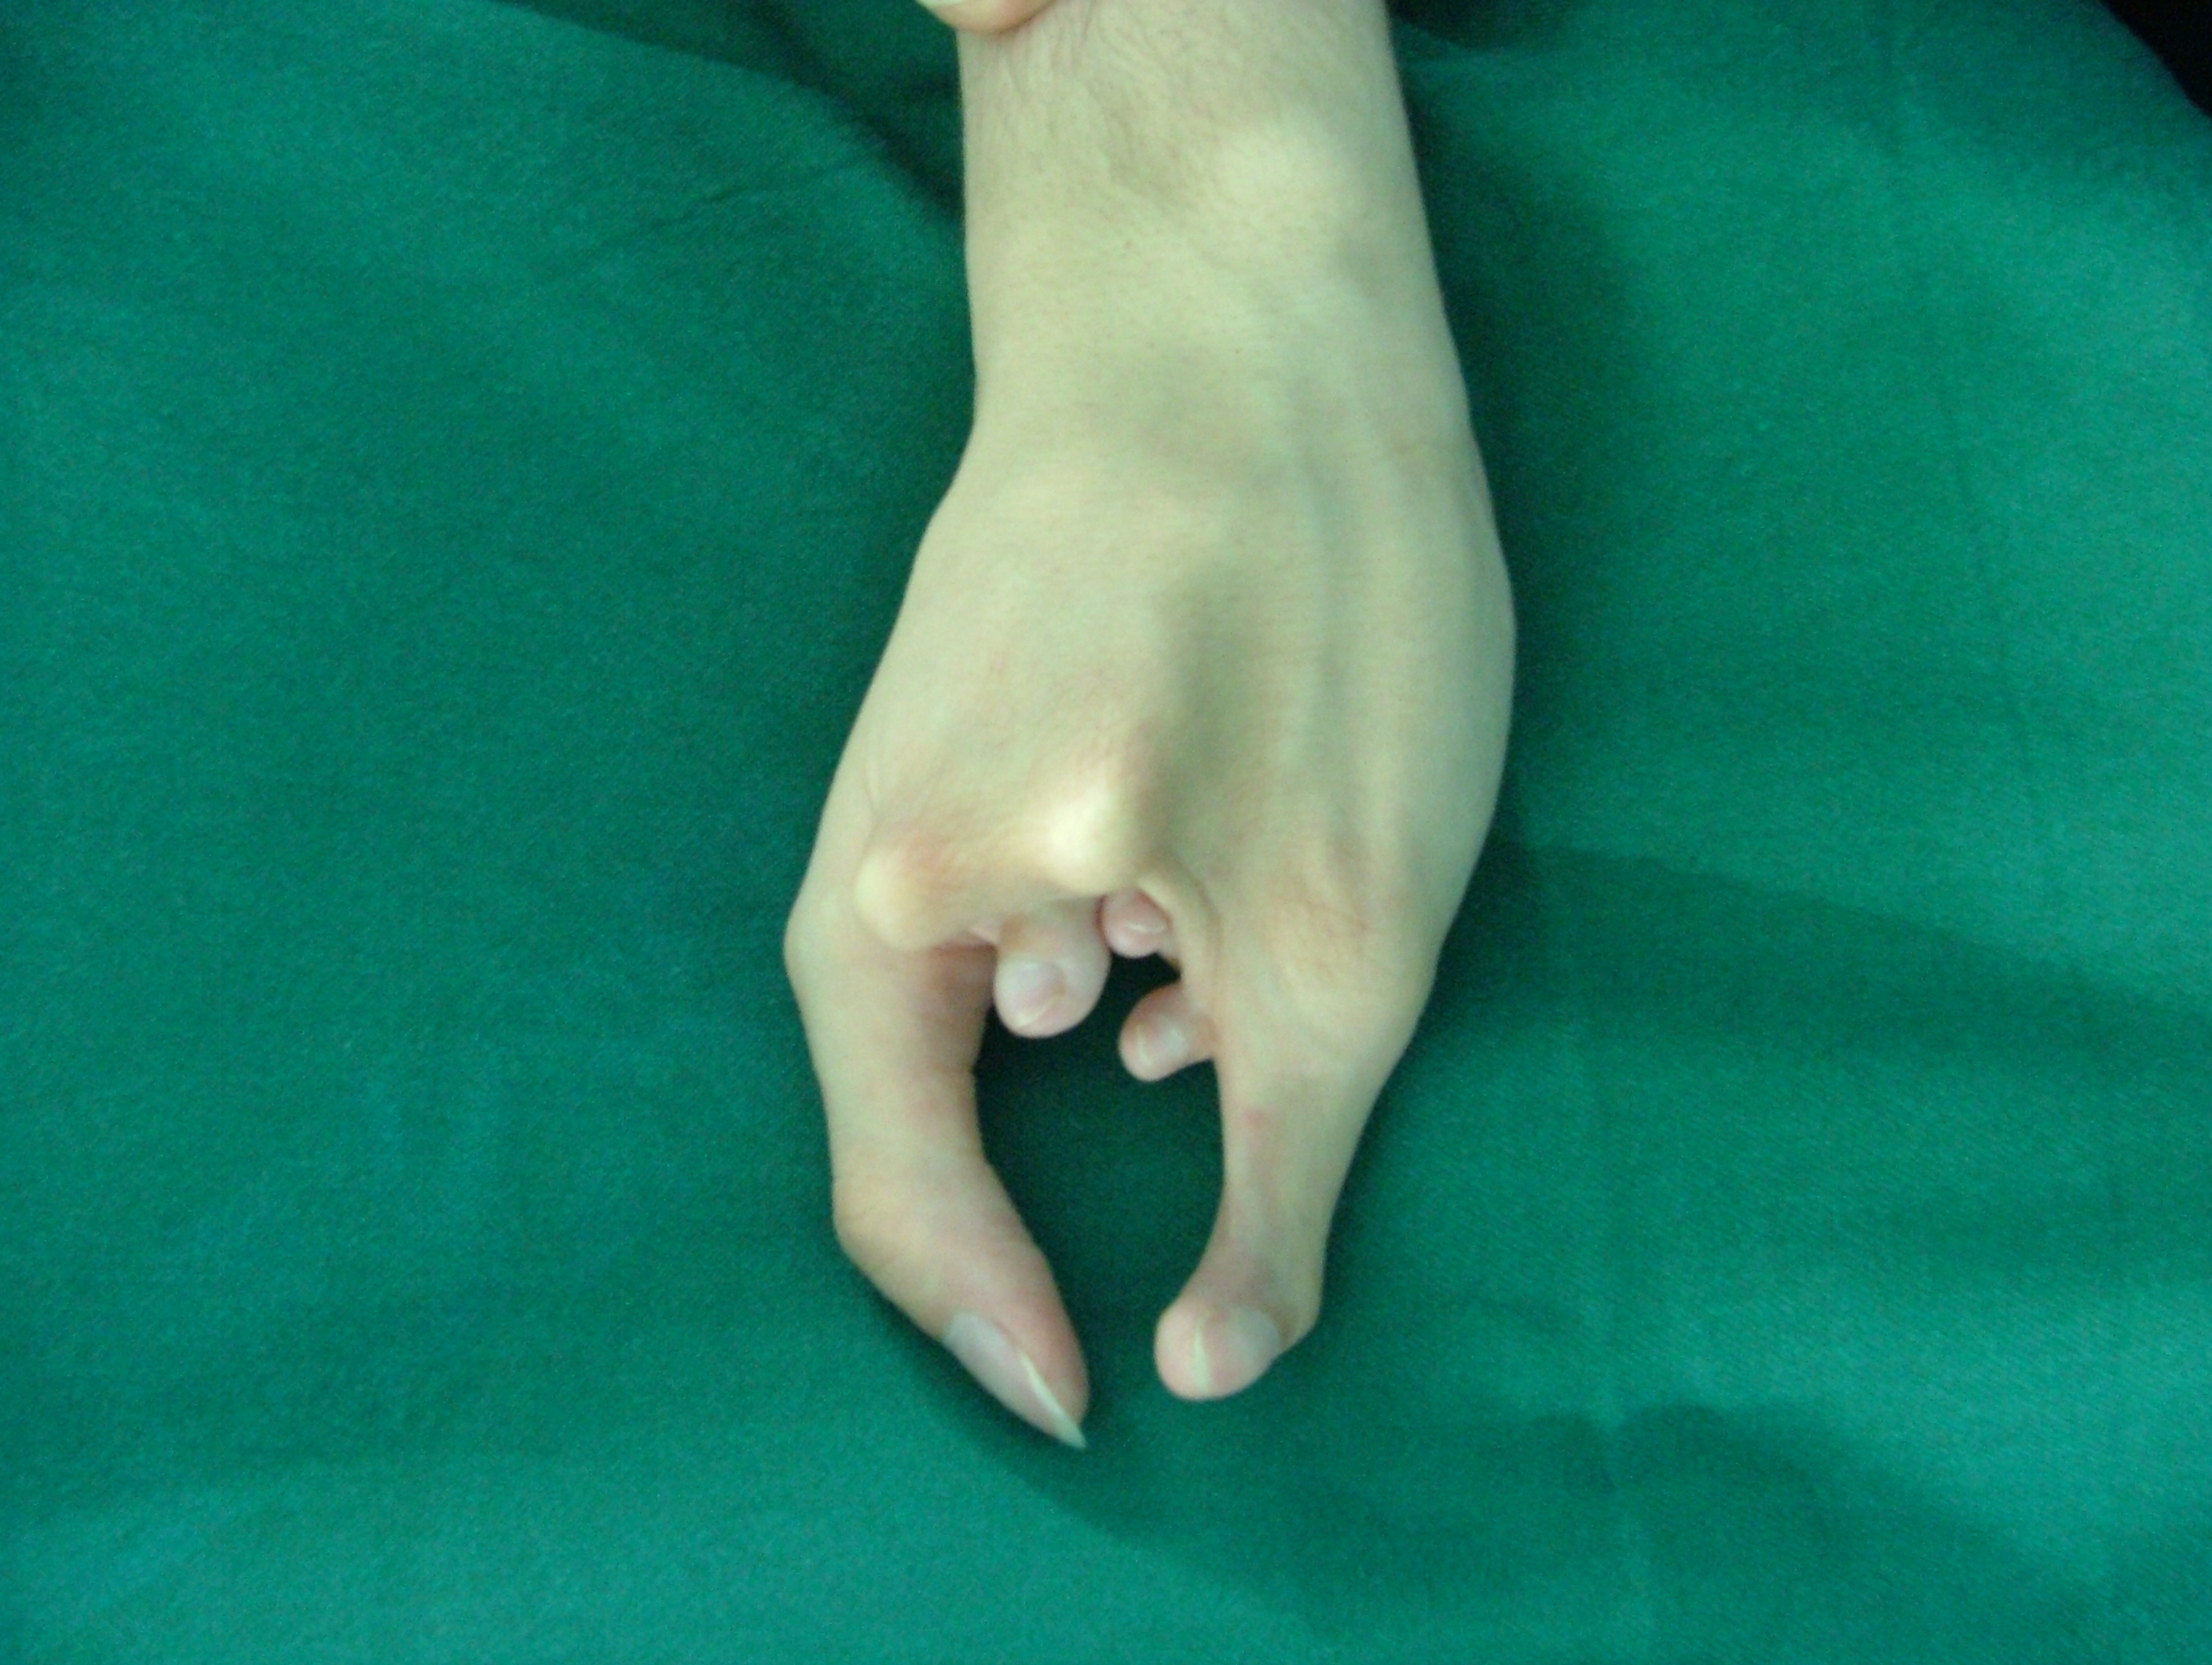

تهیه و تامین تجهیزات ارتوپدی و مشارکت در انجام اعمال جراحی ارتوپدی و عمل‌های نادر عضو تیم جراحی افزایش قد -جهت ترمیم شکستگی های قدیمی و جوش نخورده گی ها -طویل کردن اندامها- طویل کردن انگشت قطع شده - تعویض مفصل لگن _تعویض مفصل زانو _ بازسازی رباطACLوPCL_اصلاح ناهنجاریهای مادر زادی -با همکاری پزشکان و متخصصان مجرب آموزش دیده در روسیه و اتریش و سوئیس بروش جراحی ایلیزاروف و lon و lsa و واگنر و اسلایدینگ نیز جدید ترین روش افزایش قد و اندام در سال 1397 بنام hil هیل برای اولین بار- افزایش قد به 6 روش جراحی و جدیدترین روش در اروپا و روسیه. آدرس مطب _تهرانسر بلوار اصلی مجتمع سهند طبقه4 واحد 410